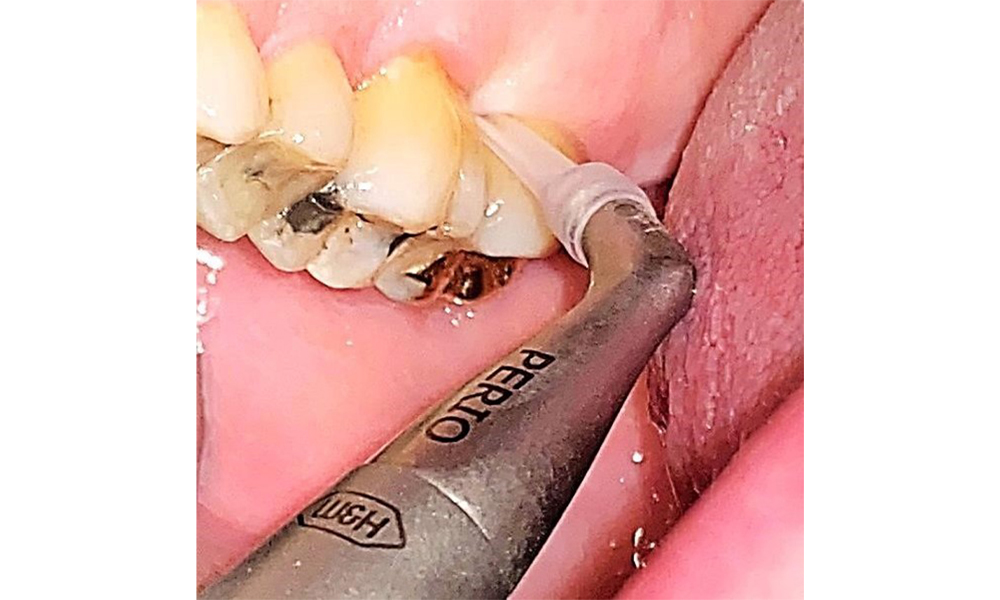

Използване на ултразвуков накрайник за отстраняване на твърда минерализирана плака (скалер Proxeo Ultra с перио накрайник, W&H).

Фиг. 9: Използване на ултразвуков накрайник за отстраняване на твърда минерализирана плака (скалер Proxeo Ultra с перио накрайник, W&H). © д-р Р. Крапф